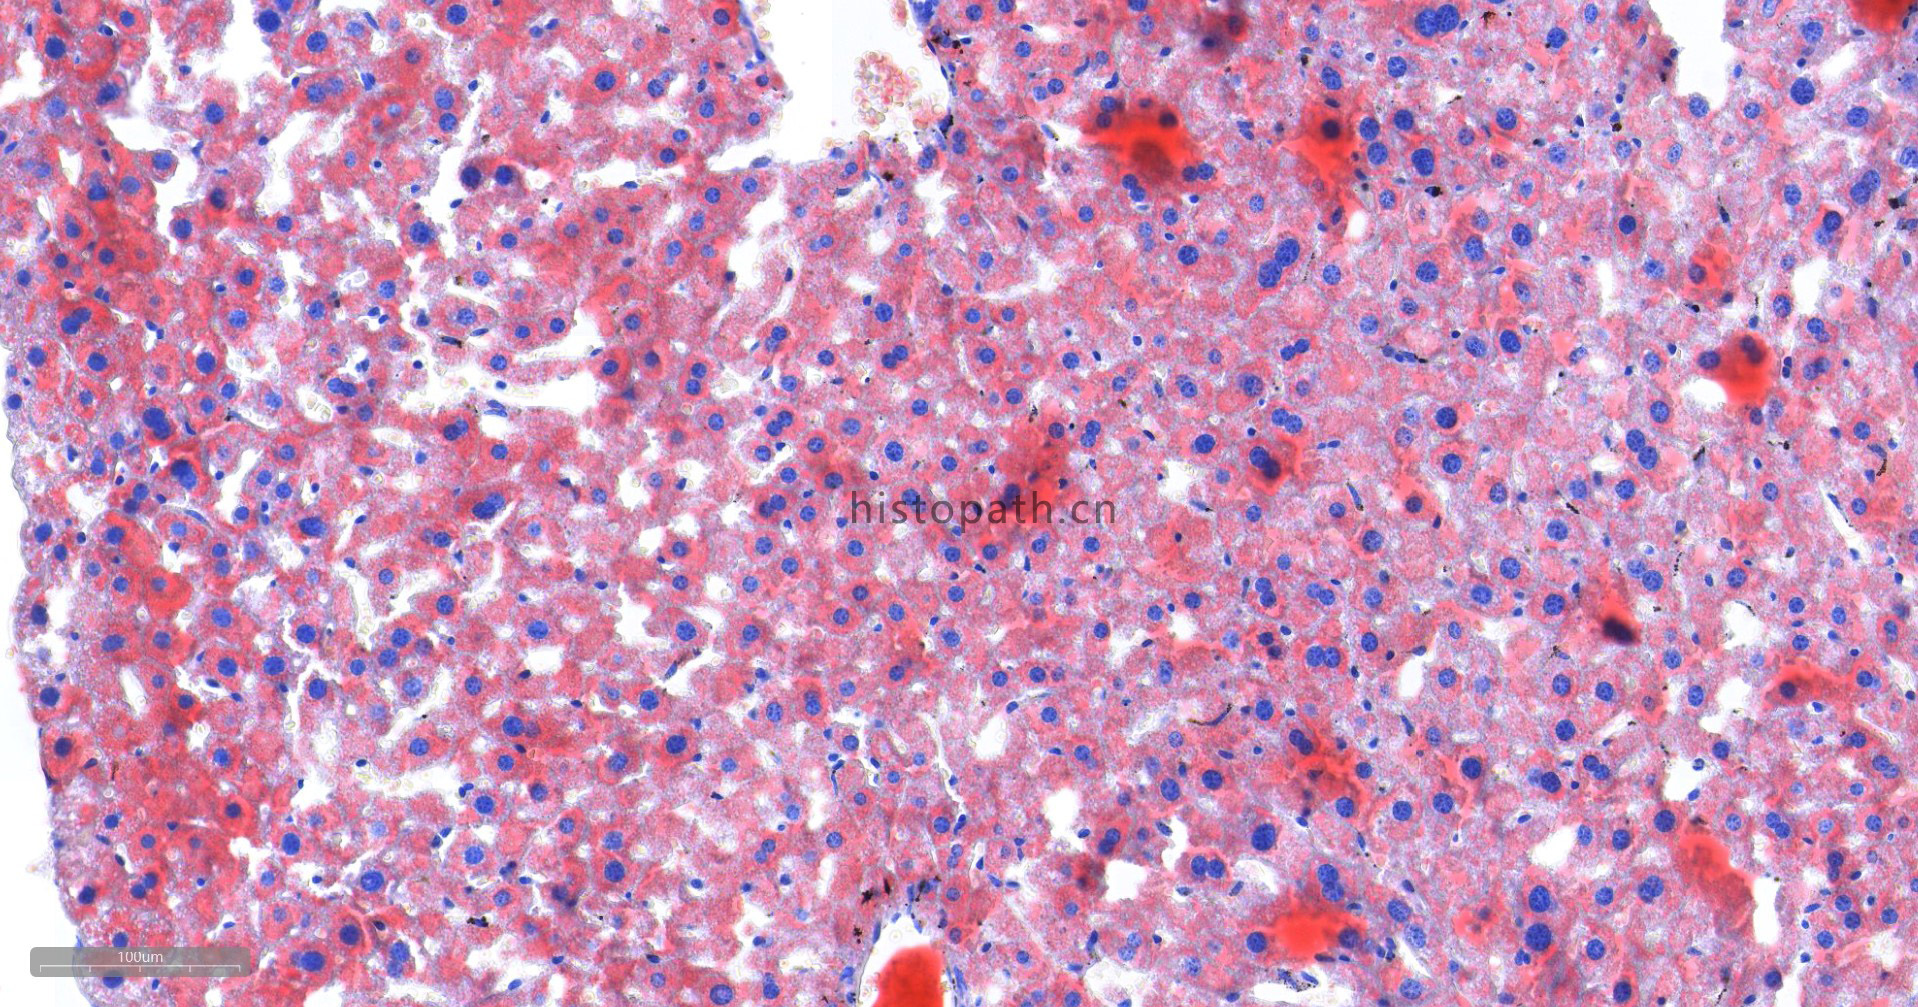

染色结果分析:中性脂肪呈橙红色,细胞核呈蓝色。